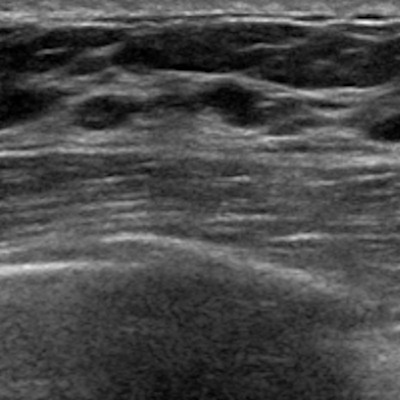

Previous studies suggest that ABUS has advantages over conventional breast ultrasound, including providing high-resolution 3D images with multiplanar reformations and reducing operator dependence by increasing consistency and reproducibility. However, the researchers pointed out that ABUS still has its share of disadvantages. These include generating volumetric image data with many slices, which can cause oversight errors. It also has limited ability to assess the axilla, vascularity, and elasticity of lesions.

For the study, the researchers included data from 262 ABUS-detected breast lesions in 231 women taken between 2020 and 2022. Of the total, 145 lesions were malignant, while 117 were benign. From there, two radiologists reviewed the images and assigned a BI-RADS category, and the AI-CAD system classified them as positive or negative.